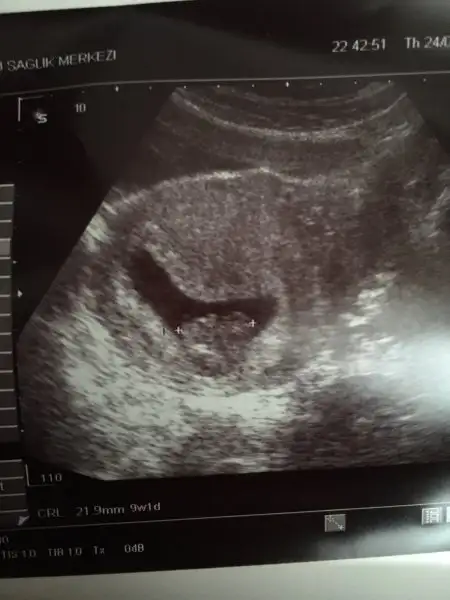

Erkek fasulye :)Eki Görüntüle 1813915 Kızlar benim fasulyem Hakkı'nda ne düşünüyorsunuz

Şimdi sitelerde dolaşıyordum da kese de nub da erkek gibi görünüyor. Ben mi yanlış görüyorum. Allah bağışlasın kız dimi bebeğinBu da benim minis .. bakalım bende öğrenince yazarım..

Hayırlısı olsun inşallah teşekkürler yorum içinErkek fasulye :)